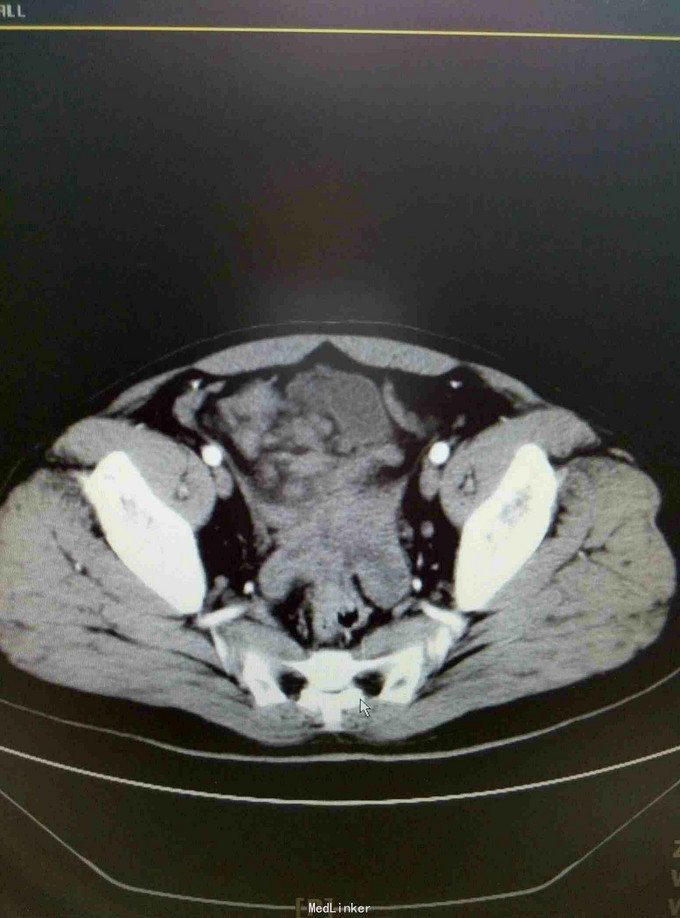

患者15年6月因腹胀就诊某医院行CT:疑似自发性腹膜炎,给予抗炎治疗。9月15日送检腹水发现增生间皮细胞。后去省影像中心行CT示:腹膜广泛增厚,强化,符合转移。后就诊我院腹膜肿物穿刺病理:促结缔组织增生性小园细胞瘤。后期贝伐单抗,IFO,THP,VCR,治疗。目前治疗中……